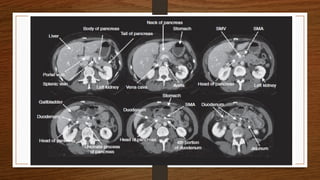

To understand the anatomy and physiology of the pancreas